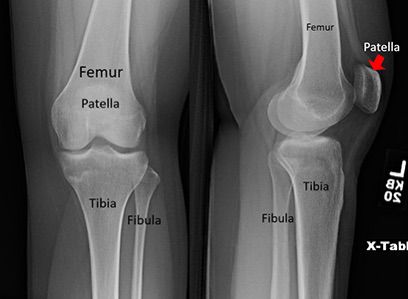

Understanding Knee Fractures

A knee fracture refers to a break in any of the bones forming the knee joint—typically the distal femur (thigh bone), proximal tibia (shin bone), or patella (kneecap).

Robotic assisted knee surgery procedure image 2 Robotic assisted knee surgery procedure image 3 Robotic assisted knee surgery procedure image 4 Robotic assisted knee surgery procedure image 5